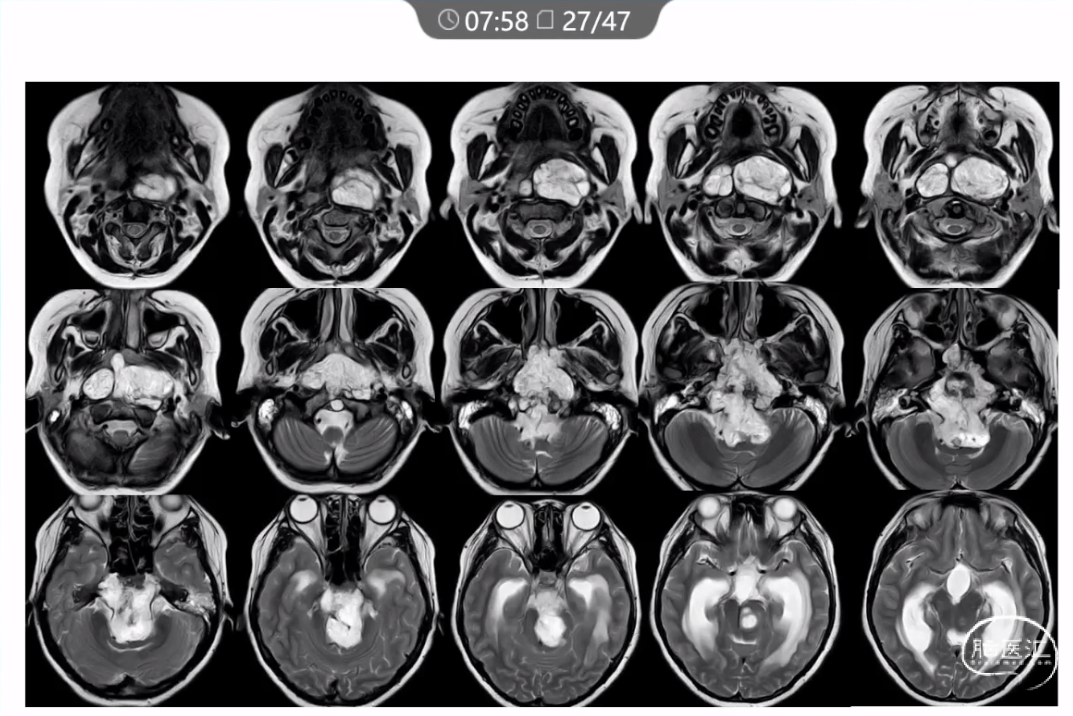

本文主要内容为:脊索瘤临床特点、治疗选择,以及多个手术病例。